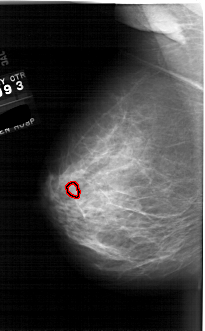

A_1761_1.LEFT_CC

LEFT_CC LINES 6526 PIXELS_PER_LINE 3601 BITS_PER_PIXEL 12 RESOLUTION 43.5 OVERLAY

FILE: A_1761_1.LEFT_CC.OVERLAY

TOTAL_ABNORMALITIES 1

ABNORMALITY 1

LESION_TYPE MASS SHAPE OVAL MARGINS ILL_DEFINED

ASSESSMENT 4

SUBTLETY 3

PATHOLOGY BENIGN

TOTAL_OUTLINES 1